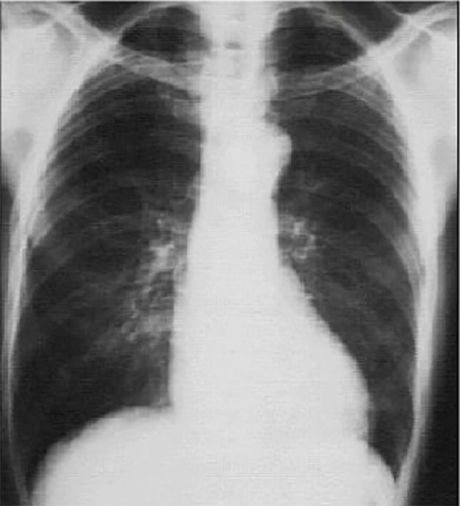

This PA chest X ray shows an aortic knob that is prominent.

It is demonstrated by the greater than normal shadow created by the transverse aorta. Note that the cardiothoracic ratio is less than fifty percent, a normal finding. The pulmonary vasculature is normal. Although left ventricular mass may be increased, there is no evidence of ventricular dilatation.